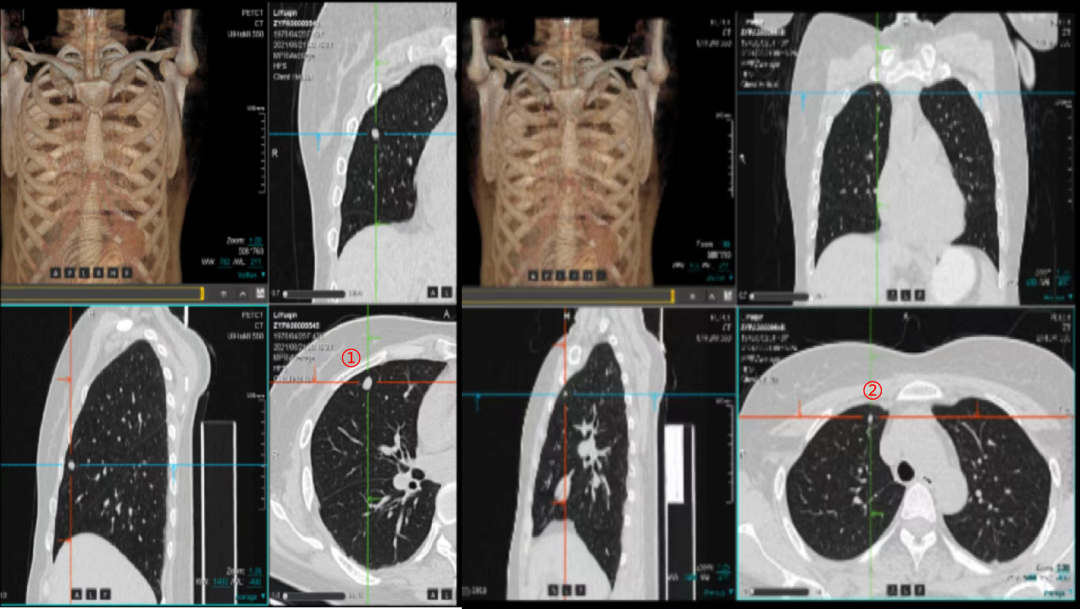

▲2021-4-12 检查项目:盆腔CT平扫(普+特)、上腹CT平扫(普+特)、胸部CT平扫(普+特)、盆腔CT强化+平扫(普+特)、上腹CT强化+平扫(普+特)和胸部CT强化+平扫(普+特)的影像表现与印象

第1次术后16个月、还纳术后11个月复查。

▲2021-5-17 检查项目:盆腔CT平扫(普+特)、上腹CT平扫(普+特)、胸部CT平扫(普+特)、盆腔CT强化+平扫(普+特)、上腹CT强化+平扫(普+特)和胸部CT强化+平扫(普+特)的影像表现与印象

第1次术后19个月、还纳术后14个月复查。

▲2021-8-12 检查项目:盆腔CT平扫(普+特)、上腹CT平扫(普+特)、胸部CT平扫(普+特)、盆腔CT强化+平扫(普+特)、上腹CT强化+平扫(普+特)和胸部CT强化+平扫(普+特)的影像表现与印象